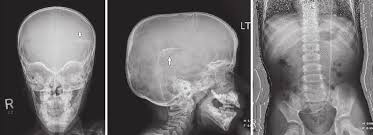

Plain X Ray Shunt Series Ap Anteroposterior A Ap Skull Xray That Download Scientific Diagram

Normal Shunt Series Radiology Case Radiopaedia Org